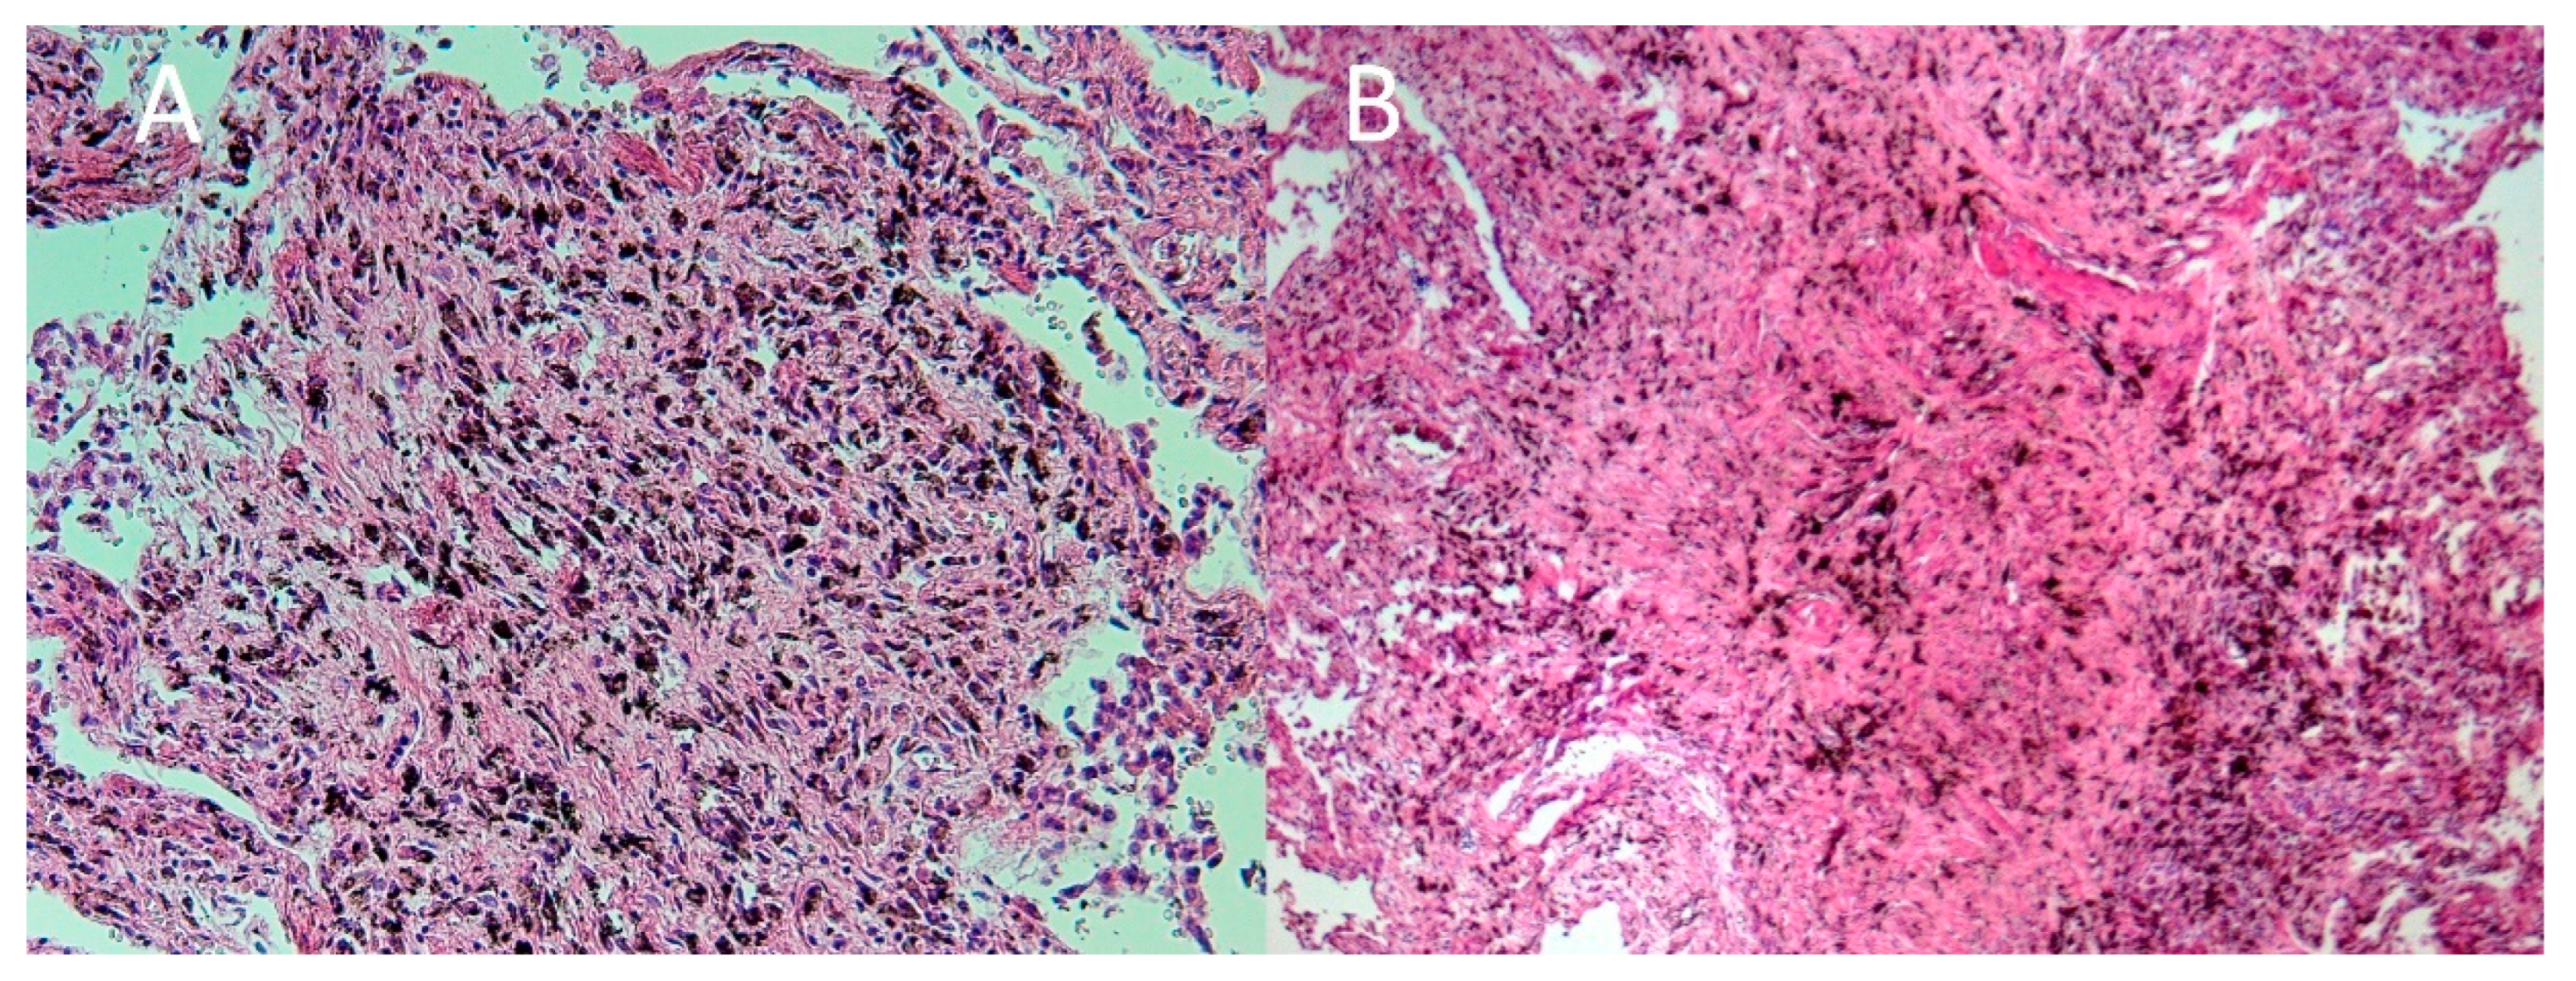

2. Case Report

3. Autopsy